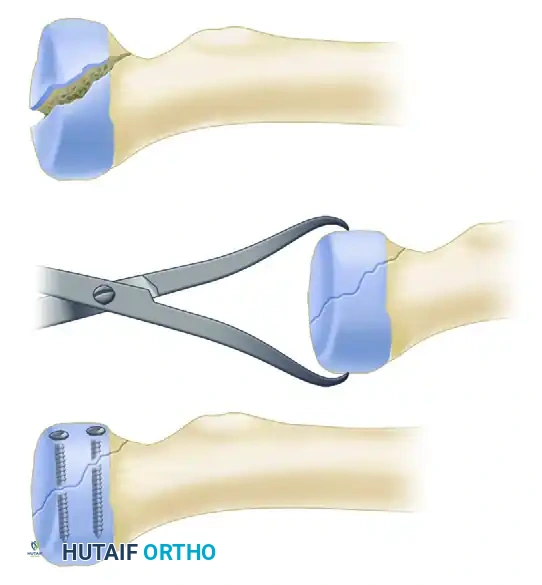

Large Fragments (Type II and III):

Larger coronoid fragments provide a critical bony buttress and must be rigidly fixed. This is typically achieved using cannulated lag screws directed from the posterior aspect of the ulna into the coronoid fragment, or occasionally from anterior to posterior if a separate medial approach is utilized.

FIGURE 57-62 B: Lag screws can be used to achieve rigid interfragmentary compression for larger coronoid fragments.

FIGURE 57-67 C: Diagram showing reduction and fixation of a large coronoid fragment with two countersunk screws.

- Open Reduction Internal Fixation (ORIF): Indicated for simple fracture patterns (typically <3 fragments) where rigid fixation can be achieved with headless compression screws or a low-profile plate.